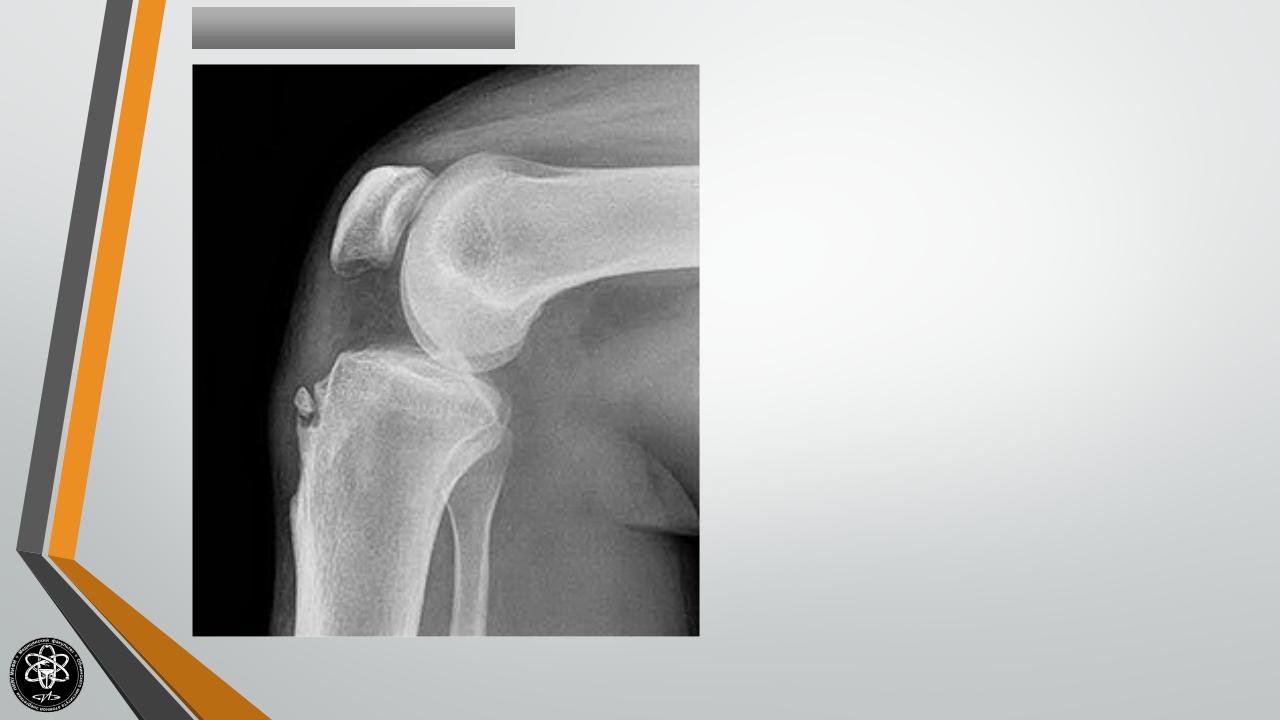

Остеохондропатия

бугристости

БолезньОсгуд-Шлаттера

большеберцовой

кости.

Болезнь

развивается в возрасте 12-15 лет, чаще

болеют мальчики. Постепенно возникает

припухлость в области поражения.

Пациенты

жалуются

на

боли,

усиливающиеся при стоянии на коленях и

ходьбе по лестнице. Функция сустава не

нарушается

или

незначительно.

Лечение остеохондропатии консервативное, проводится в амбулаторных условиях. Пациенту назначают ограничение нагрузки на конечность (при сильной боли ношение ортеза на 6-8 недель), физиолечение (электрофорез с фосфором и кальцием, парафиновые аппликации), витаминотерапию.

Остеохондропатия протекает благоприятно и заканчивается выздоровлением в течение 1-1,5 лет.